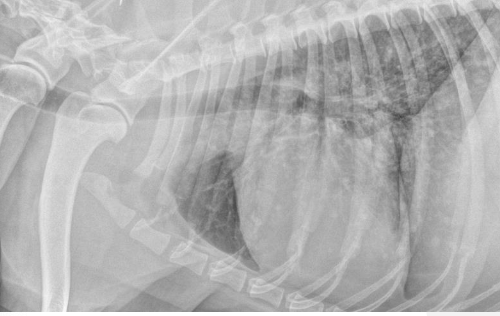

-thoracic imaging (radiographs or CT)

-abdominal imaging (radiographs, ultrasound, or CT)

what is the purpose of thoracic imaging when diagnosing hemangiosarcoma?

search for mets:

-described as nodular to interstitial coalescing miliary pattern (ill-defined, fuzzy appearance)

radiographs: 78% sensitivity for detecting mets (false negative rate decreases w/ 3 views)

what will be seen on abdominal radiographs in patients with hemangiosarcoma?

nonspecific: mass

loss of serosal detail